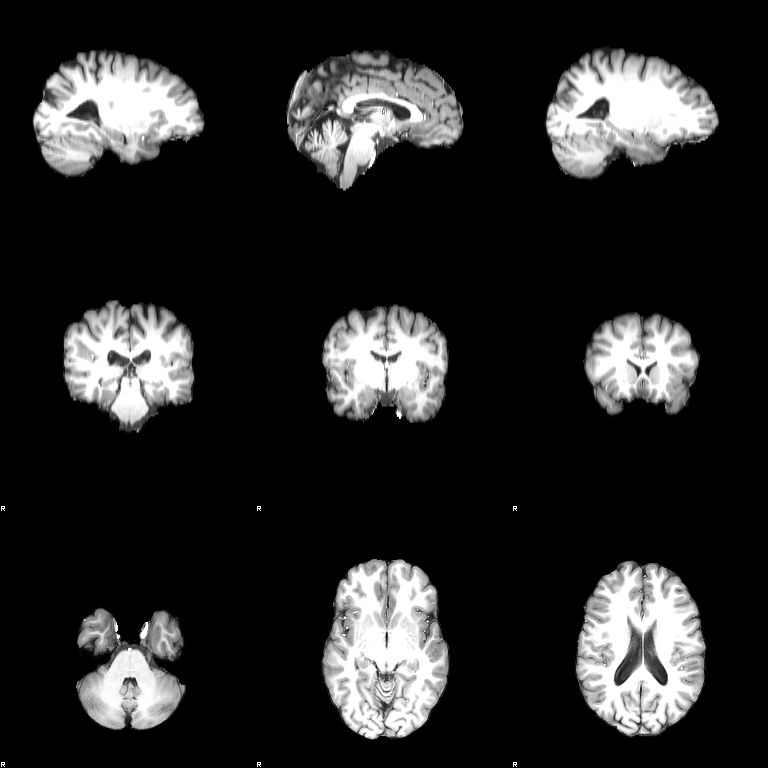

BET

Set the Input image to be structural and press OK. The output will be structural_brain. You will see a message on your terminal when BET has finished.